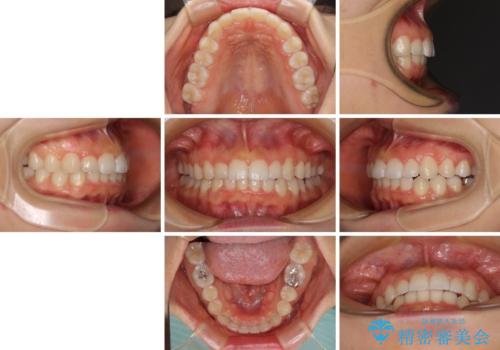

前歯のデコボコと突出感 インビザラインによる矯正治療

- 上下前歯のデコボコと、上顎前歯の突出感を気にして来院された患者様です。

インビザラインによる上下歯列の側方拡大と後方移動、IPR(歯と歯の間を削る)にるスペースの獲得により歯列を整えることとしました。

毎日22時間以上しっかりとマウスピースを装着していただいたので、スムーズに治療が進みました。歯と歯の間を削ることでうまくスペースコントロールでき、1年強で終えることができました。